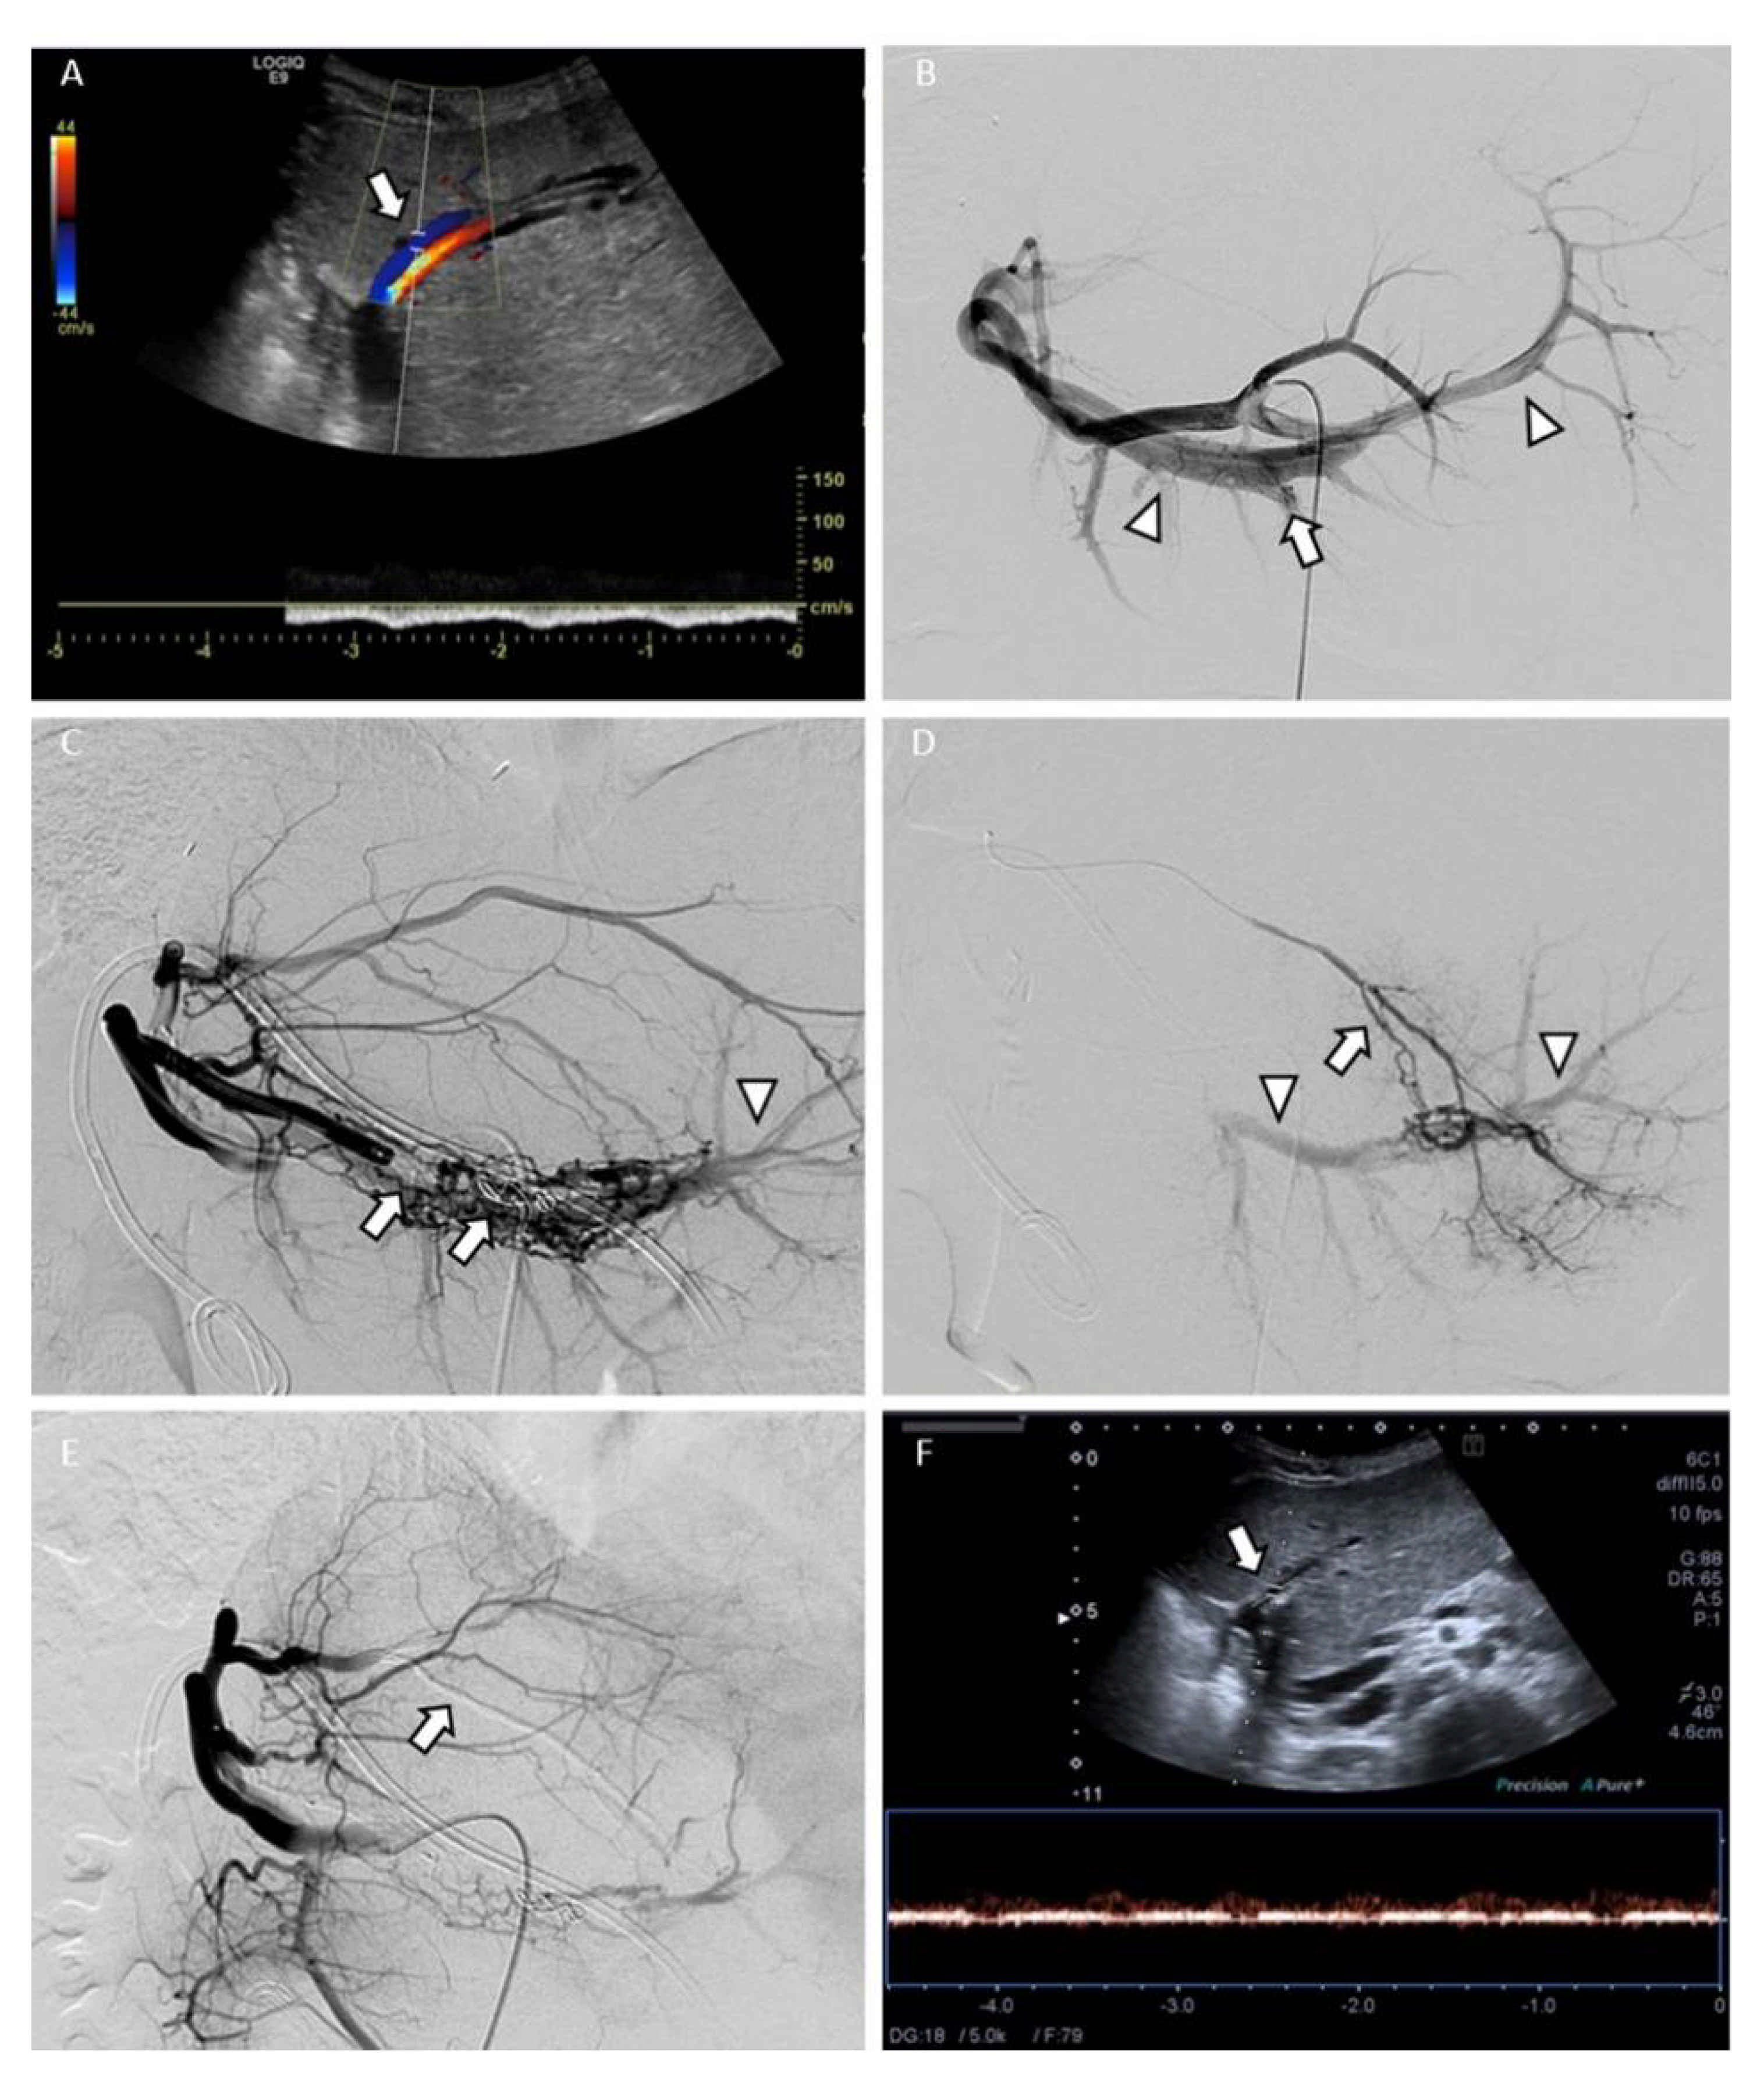

| 1 | 11 | M | CDUS | 10 | 1 | iatrogenic (biopsy) | yes | no | 0.35 | segmental | hemobilia | yes | 9 | good, APF reduction |

| 1 | endovascular, twice | 15 | d-coils, MVP, Onyx | none | 0.35 | segmental | yes | yes | yes | yes | 0.4 | sub-segmental | yes |